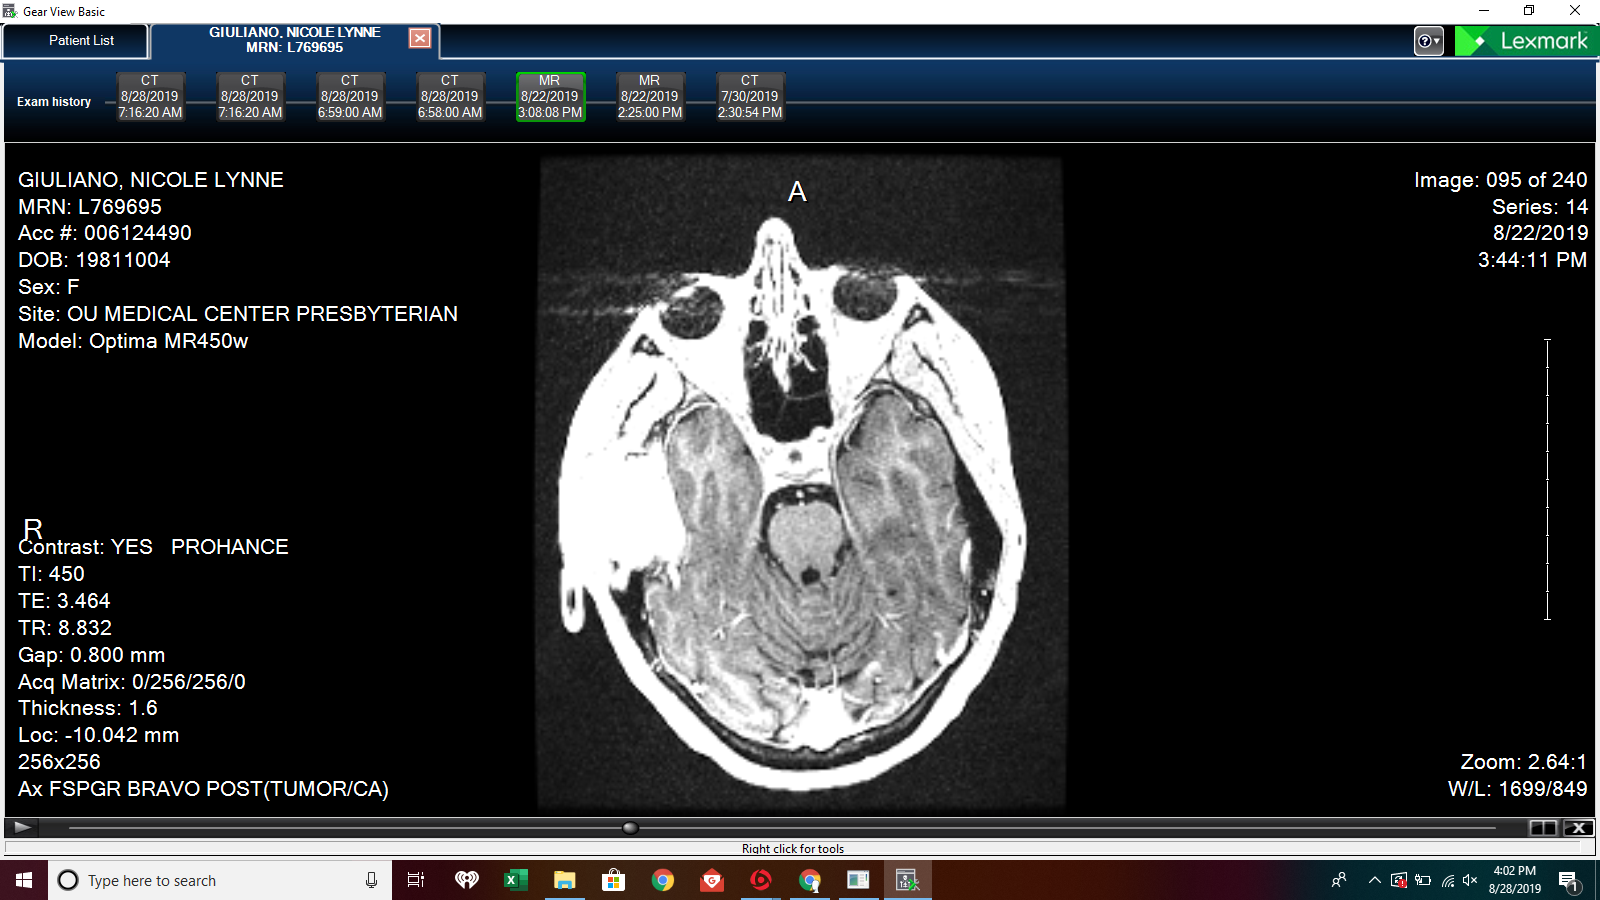

Next Set of Scans Scheduled Leave a Comment / By Nicole / August 15, 2019 MRI and specialty CT (will be used to reconstruct my skull for replacement part) scans will happen next week…I will be 2 steps closer to scheduling surgery to remove this beast! Update: some additional scans Related Posts Getting Closer to Setting a Surgery DatePost Surgery Update – Improved Face MovementOnly 2 Days Until Neo Leaves the Matrix!Update After Oral Surgeon Appointment How This Week’s Appointments WentHow Am I Feeling Today?Woman Terrified to Wash Hair Post Head SurgerySurgery is SCHEDULED!